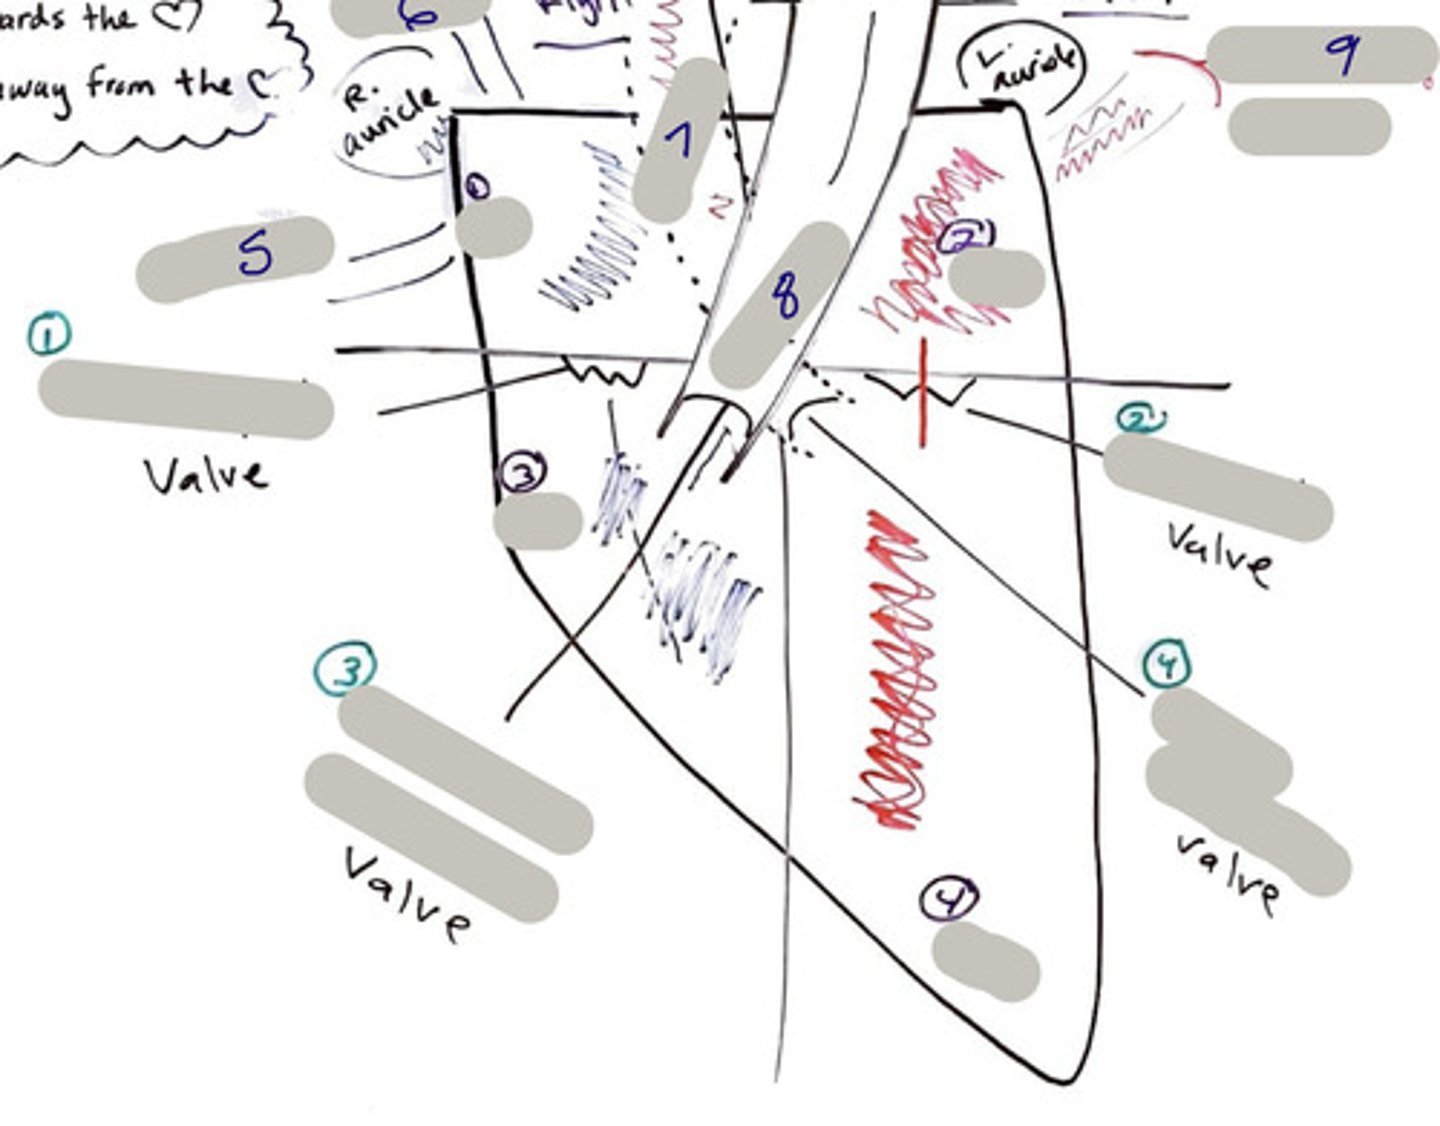

Tricuspid Valve (Right Atrioventricular Valve)

1-valve

Bicuspid valve (Left Atrioventricular Valve)

2-valve

Pulmonary Semilunar Valve

3-valve

Aortic Semilunar Valve

4-valve

Right Atrium

1-chamber

Left Atrium

2-chamber

Right Ventricle

3-chamber

Left Ventricle

4-chamber

Inferior Vena Cava

5-A vein that is the largest vein in the human body and returns blood to the right atrium of the heart from bodily parts below the diaphragm.

Superior Vena Cava

6-A vein that is the second largest vein in the human body and returns blood to the right atrium of the heart from the upper half of the body.

Aorta

7-The large arterial trunk that carries blood from the heart to be distributed by branch arteries through the body.

Pulmonary Trunk

8-carries blood from right ventricle to pulmonary arteries

Pulmonary veins

9-a vein carrying oxygenated blood from the lungs to the left atrium of the heart.